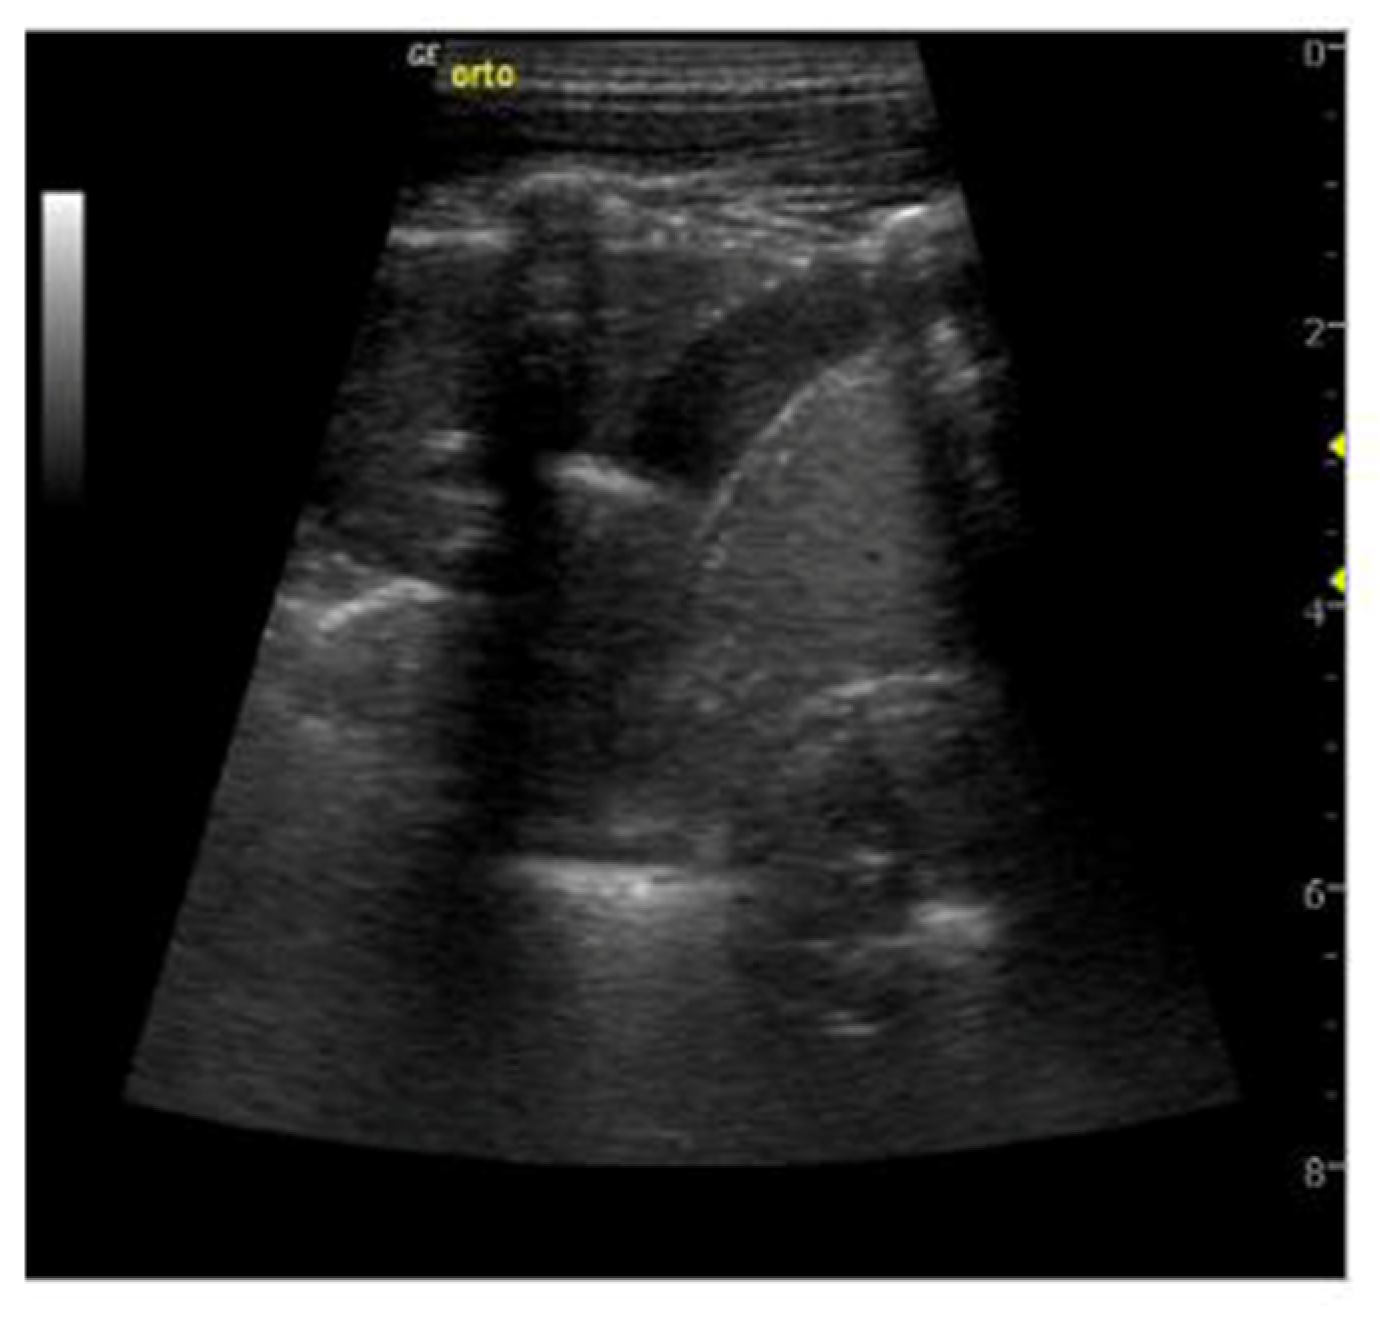

| Pleural effusion | Hypo- or anechogenic structure, delineated by the chest wall and the diaphragm [11,26] |

| B-lines | Vertical reverberation artefacts from the pleural line to the edge of the scree; laserlike, vertical hyperechogenic artefacts synchronized with pleural line [11,23,27] |